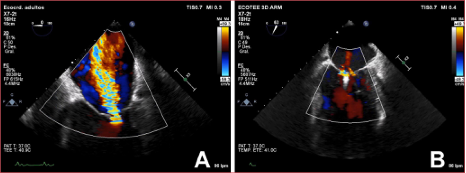

Figura. Caso 1. Ecocardiograma transesofágico doppler color antes de la implantación del MitroClip® (A) y después (B).

al tratamiento médico. En el ecocardiograma transesofágico, se observa una

mejoría parcial de la función sistólica de ventrículo izquierdo con fracción de

eyección del ventrículo izquierdo del 25% e IM grave secundaria (grado IV/IV).

Debido a la persistencia de la congestión pulmonar, se plantea la corrección de

la IM y, dado el elevado riesgo quirúrgico (EuroSCORE II 16%), se decide

reparar la IM por vía percutánea, mediante la implantación de un MitraClip®.